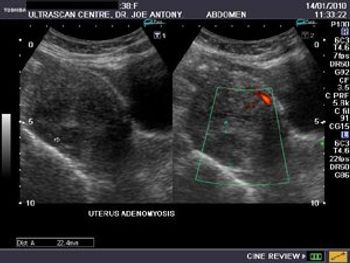

Is this lesion a fibroid or adenomyosis? Patient is a young (38n yr. old) married female with a history of dysmenorrhea and polymenorrhoea.

Cystic spaces in the sub-endometrial myometrium of the fundus.